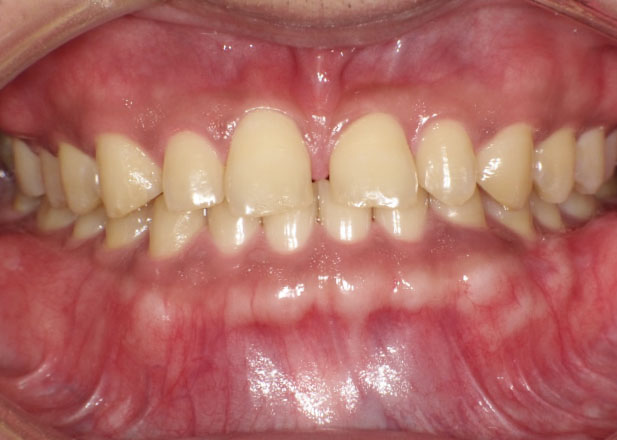

すきっ歯を治したい

正中離開(すきっ歯)は年齢とともに進行しやすいです。進行をとめるためには見た目の改善だけではなく、全体のかみ合わせを整えることが重要です。

口腔内写真

治療前

主訴 正中離開(すきっ歯)を治したい。